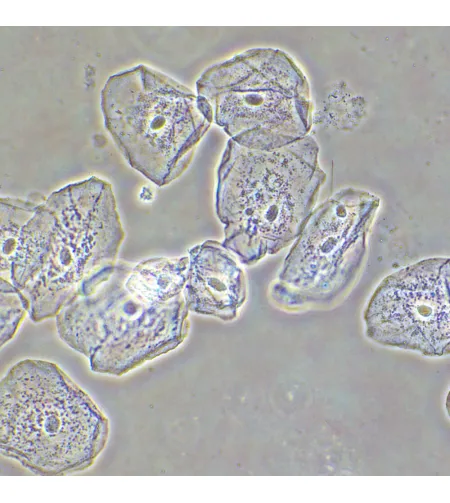

MAGUS SPH2 faasikontrastsuseadme koosneb faasikontrasti liugurite komplektist, faasikohustusega andurite komplektist ning keskendava teleskoobist. Faasikontrastsuseadet kasutatakse läbipaistvate madala kontrastsusega proovide uurimiseks, mis pole heledas väljavalguses nähtavad. Värvimine tapab elusaid rakke. Tehnika peamine eelis on see, et seda saab kasutada elusate värvimata organismide uurimiseks nende loomulikus olekus. Tehnikat kasutatakse meditsiinis, ökoloogias, farmakoloogias, põllumajanduses jne.

Faasiobjektiivid erinevad tavalistest objektiividest selle poolest, et nende väljumispupilli tasapinnal on faasiring. Tasapinnelised akromaatilised faasiobjektiivid moodustavad pilti, mille fookus on keskel ja servadel sama, seega on moonutus ebaoluline. Kroomaatilised aberratsioonid on parandatud siniste ja punaste jaoks, sfäärilised aberratsioonid - roheliste jaoks ning väli kõverus on parandatud 90% vaatevälja läbimõõdu jaoks. 10x objektiivi kasutatakse proovide uurimiseks koos kaanega või ilma. 20x, 40x ja 100x objektiive kasutatakse proovide vaatlemiseks 0,17mm kattega. 100x objektiiv toetab õli immersiooni. Objektiivid on mõeldud lõpmatu korrektsiooniga torupikkuseks. Parfokaalne kaugus on 60mm.